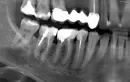

У меня треснул зуб. На снимке он со штифтом. Снимок старый. Ходила на осмотр и врач не знает что делать. Говорит, что вырвать его сейчас не получится, он стабилен, почти нет боли. Подпилила немного по высоте и отправила на снимок.

Пломба старая - лет 15. Кажется, зуб был с одной стенкой и его восстанавливали с помощью штифта и пломбы.